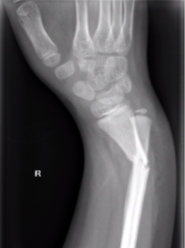

Galeazzi fracture dislocation